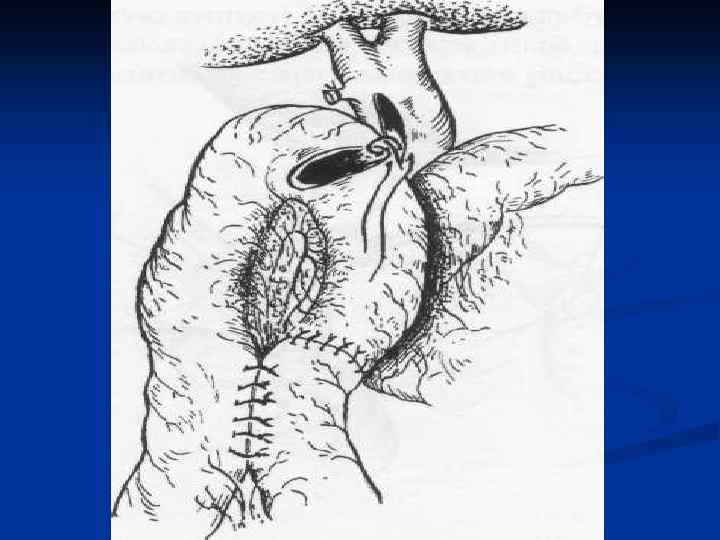

I. Восстановительные операции (восстановление проходимости протоков) 1. Эндобилиарные вмешательства под УЗИ или R – контролем (бужирование, баллонная дилатация, стентирование протоков). 2. Пластика стриктуры 3. Иссечение стриктуры с наложением анастомоза. II. Реконструктивные операции (наложение билиодигестивных анастомозов) 1. Анастомозы внепеченочных желчных протоков: а) с двенадцатиперстной кишкой (ХДА) б) с тощей кишкой (гепатико-, холедохоеюноанастомозы по Ру или по Брауну). 2. Анастомозы внутрипеченочных желчных протоков с сегментом тощей кишки, выключенной по Ру или желудком при высоких стриктурах

I. Восстановительные операции (восстановление проходимости протоков) 1. Эндобилиарные вмешательства под УЗИ или R – контролем (бужирование, баллонная дилатация, стентирование протоков). 2. Пластика стриктуры 3. Иссечение стриктуры с наложением анастомоза. II. Реконструктивные операции (наложение билиодигестивных анастомозов) 1. Анастомозы внепеченочных желчных протоков: а) с двенадцатиперстной кишкой (ХДА) б) с тощей кишкой (гепатико-, холедохоеюноанастомозы по Ру или по Брауну). 2. Анастомозы внутрипеченочных желчных протоков с сегментом тощей кишки, выключенной по Ру или желудком при высоких стриктурах